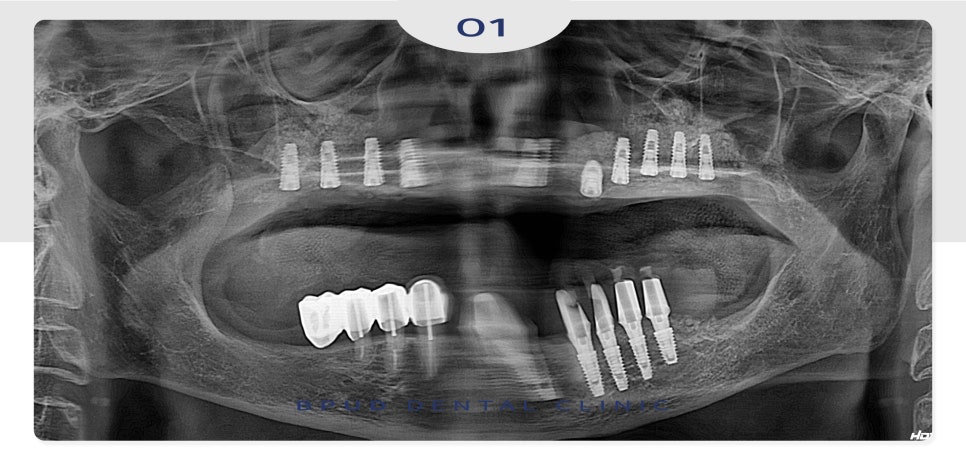

오늘은 부평역치과 전체 임플란트 수복을

진행하신 환자분을 소개해 드리려고 합니다.

환자분께서는 기존 타 치과에서

전체 임플란트가 어렵다는 말씀을 들으시고

앞니 쪽에 두 개의 임플란트를 심어

그 위에 틀니를 장착하는 방법인 오버덴쳐를

사용하고 계셨지만 최근 임플란트 부위에

통증이 느껴지고 틀니가 맞지 않아

상담을 위해 지인분께 추천을 받아

내원해 주셨는데요.

아래 앞니도 상실하였고 어금니도

흔들리는 상태에서 틀니는 너무 불편하시다며

임플란트로 치료를 희망하셨습니다.

부평유디에서는 난이도가 높은 케이스임에도

뼈이식을 동반한 전체 임플란트 식립으로

전체 수복을 완료하였습니다.